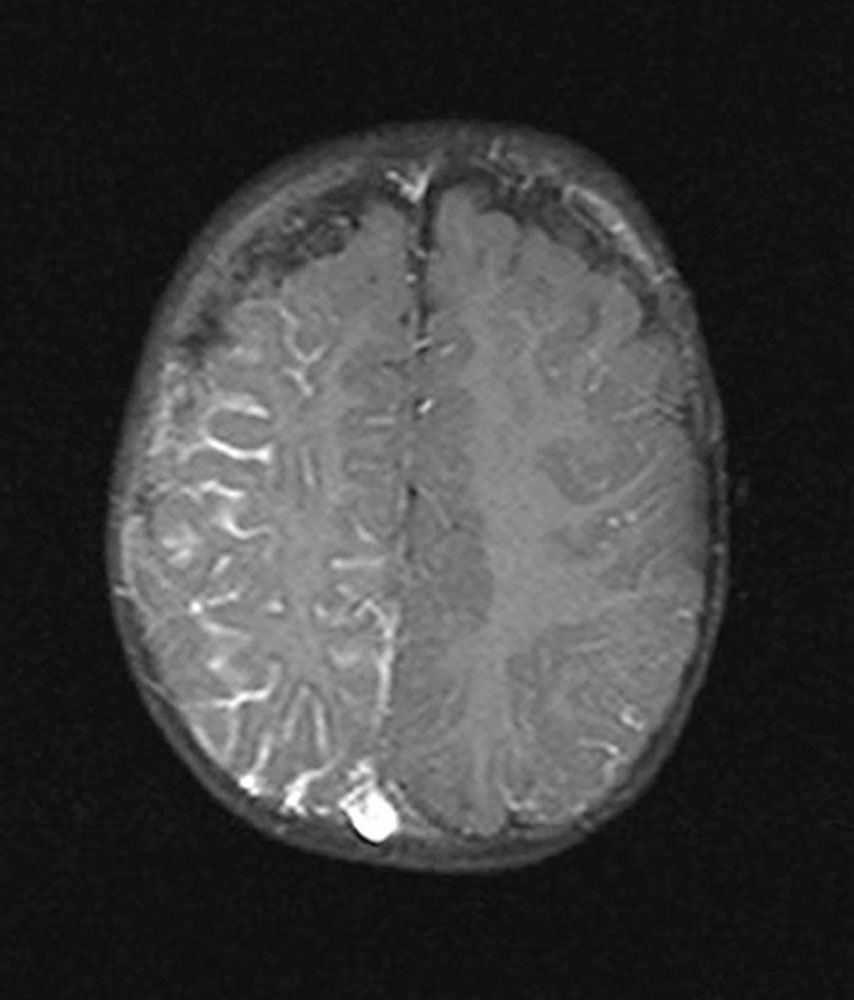

Combined capillary-venous malformations (CVM) may involve the meninges (leptomeningeal angiomatosis) and/or the choroid (choroidal angiomatosis) and lead to neurological and/or ophthalmic disorders. The occurrence of neurological symptoms (migraine, epilepsy, mental developmental disorder, less frequently: spastic hemiparesis) is quite variable. Choroidal angiomatosis may be associated with glaucoma and buphthalmos.